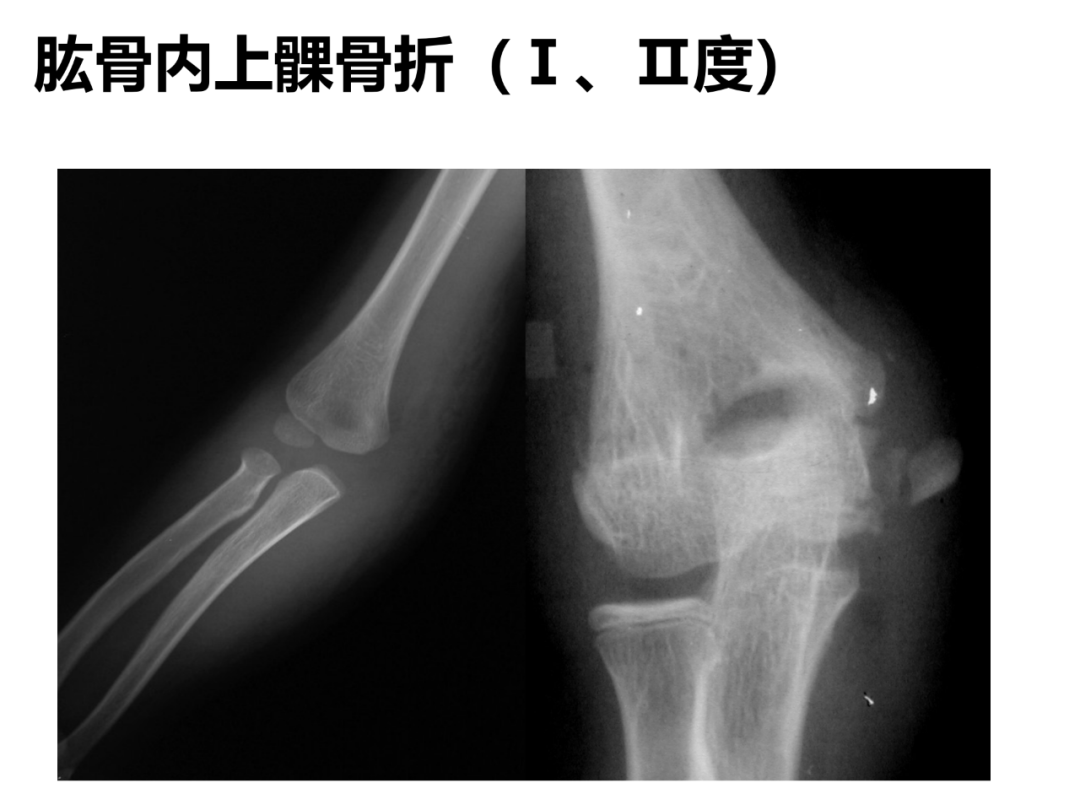

小儿骨科X线片汇总,临床读片宝典!